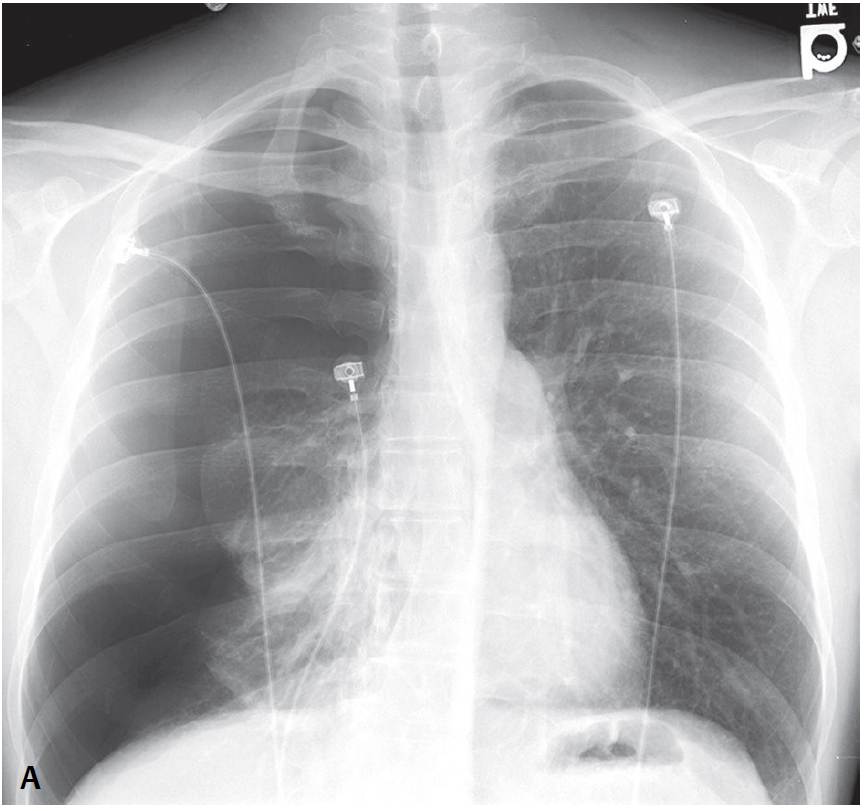

Patient with Pleuritic Chest Pain and Shortness of Breath Post category:Spot Diagnosis Post published:June 20, 2023 Share on Facebook Share on X (Twitter) Share on Pinterest Share on Email Share on Reddit Chest X-ray of a patient with pleuritic chest pain and shortness of breath 37-year-old man presents to the Emergency Department with pleuritic chest pain and shortness of breath. What’s the diagnosis ? FULL CASE AND ANSWER Share on Facebook Share on X (Twitter) Share on Pinterest Share on Email Share on Reddit Read more articles Previous PostFever, Rash and Tongue Changes Next PostReversible Facial Congestion After Elevation of Both Arms You Might Also Like A Diagonal Crease in Each Earlobe September 7, 2021 Patient with Hypercalcemia and Suppressed Parathyroid Hormone Level October 4, 2021 Phlegmasia Cerulea Dolens (Deep Vein Thrombosis) May 10, 2021